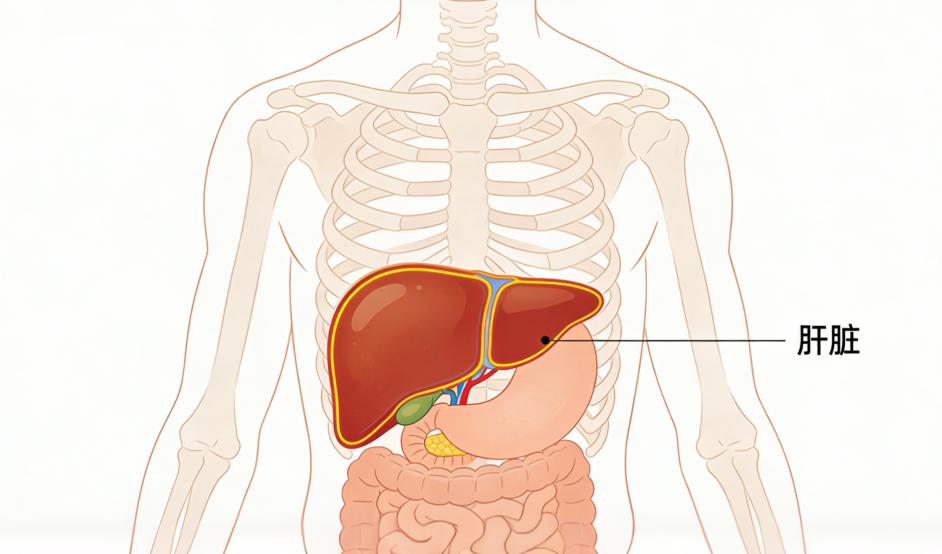

肝病是全球公共卫生的重要挑战。据统计,全球约有8亿人受慢性肝病困扰,其中我国患者超过3亿。除病毒性肝炎外,肥胖、代谢相关性脂肪肝、酒精性肝病、自身免疫性肝病以及某些遗传代谢性疾病,也是导致肝病常见的原因。

在我国,乙型肝炎尤为突出。根据国家卫健委2019年数据,我国乙肝病毒感染者约7000万,其中慢性乙型肝炎患者约2000万至3000万。乙型肝炎之所以令人担忧,是因为其中约三分之一可能发展为慢性肝炎,而这些慢性患者中又约有三分之一可能进一步进展为肝硬化甚至肝癌。

疾病可表现为乏力、恶心、食欲不振、厌油、腹胀、尿黄、肝区不适等症状,严重者可出现肝掌、蜘蛛痣,甚至意识改变、嗜睡等神经系统症状。若未能有效控制,病情可逐渐进展为肝硬化或肝癌。

由于肝脏代偿能力较强,早期常无明显症状,发现时往往已进入中晚期。传统药物治疗存在一定局限性,因为多数药物需经肝脏代谢,不恰当的用药反而可能加重负担。对于终末期肝病,肝移植是目前有效手段,但面临供体短缺、免疫排斥等问题。